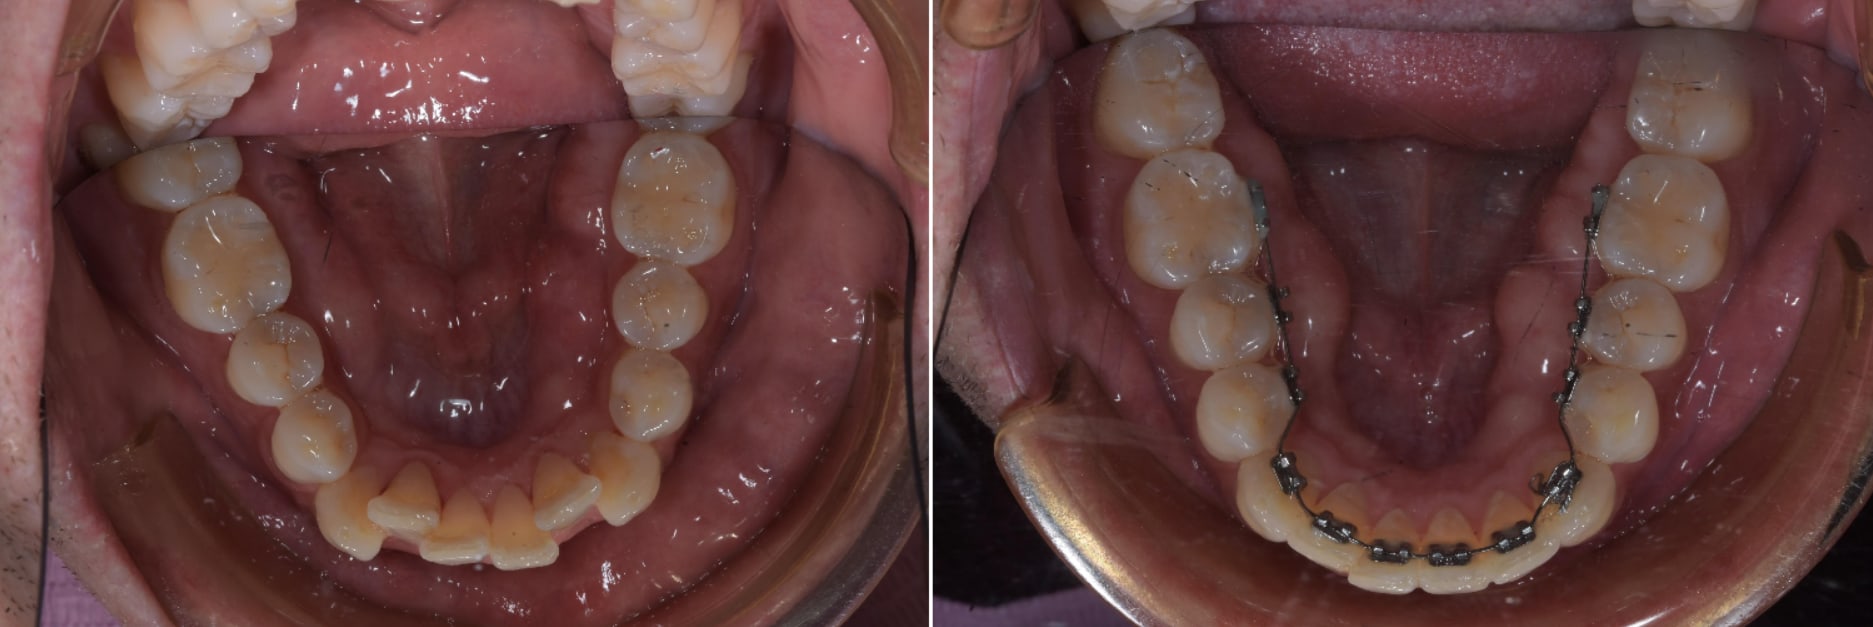

Si joint une photo d'un cas de fixe que j'ai finie avec du plastique. Cas réalisé sans 3D juste ne modifiant le modèle en plâtre ( tu meules là ou tu veux poussé et tu met de la résine pour faire de la place là ou la dent doit bouger.

Si j'avais à refaire ce cas je le traiterais exactement de la même maniére. Mouvement simple à réaliser avec une force unitaire.

Ici un cas de lingual 2D débagué hier ( 4 mois de traitement ) .

Si joint le set up initial avec après une série de quatre gouttière et les photo initial et 4 semaine plus tard. Je n'avais pas encore le module d'attache quand j'ai fait ce cas, donc j'avais fait les attaches avec du composite directement en bouche.

Pour ceux qui font un peut d'aligner vous devez savoir que les rotations des incisives inf peuvent être très délicate ( quasiment pas de surface pour transmettre la force ). Donc ici je l'avais joué safe en mettant 5° de rotation sur quatre gouttière ( invisalign aurait probablement fait 8° sur quatre aligner ) .